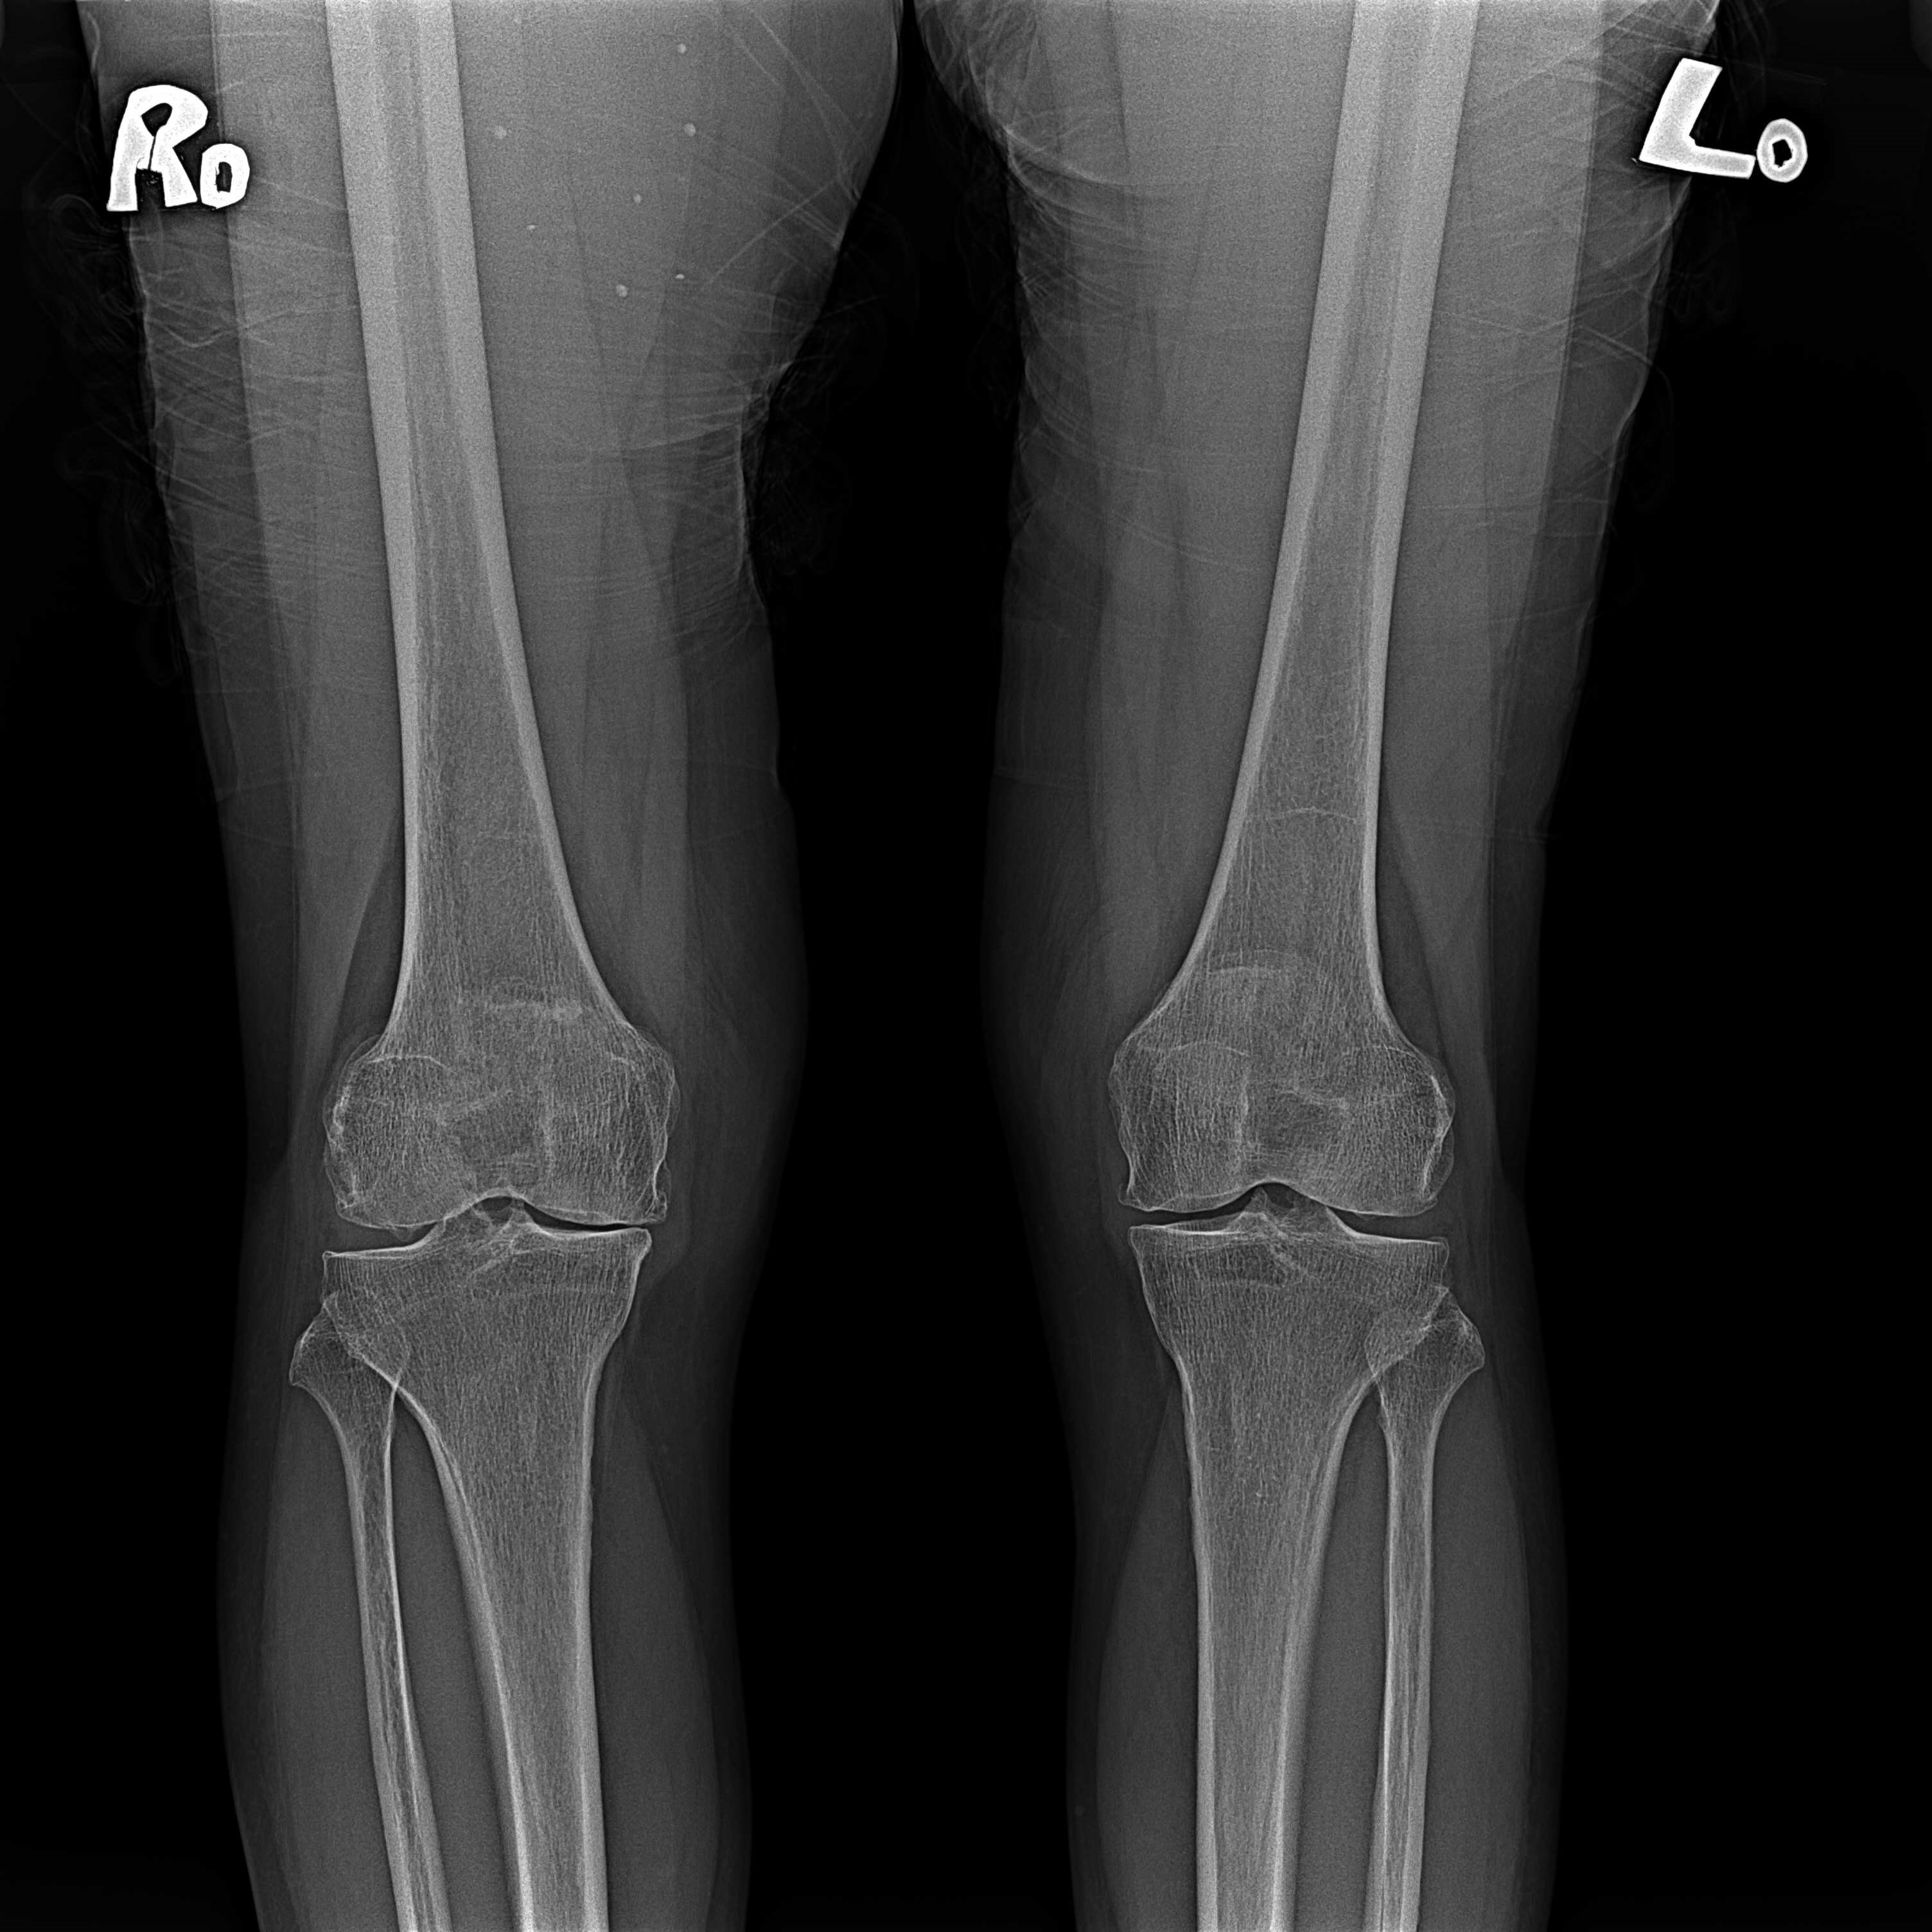

機器手臂手術 首頁 案例分享 膝關節手術 機器手臂手術 蔡女士 78歲 術前 術後 陳女士 70歲 術前 術後 術前 術後 ANGEVINE女士 73歲 術前 術後 U.S.A Mark 73歲 術前 術後 藍女士 78歲 術前 術後